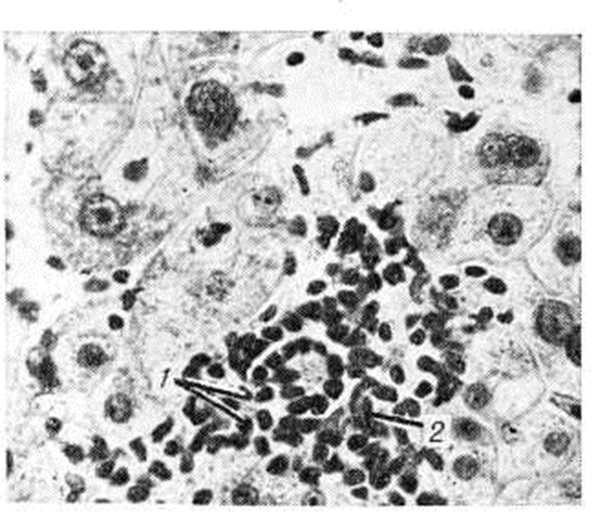

Хронический очаговые Гепатит (например., при бруцеллёзе, саркоидозе, туберкулёзе, альвеококкозе) имеют специфическую патологический картину, свойственную общей патоморфологии этих заболеваний (рисунок 1—4).

При поражении печени некоторыми грибками (актиномикоз), простейшими (амебиаз, балантидиаз) и гельминтами (аскаридоз, клонорхоз, фасциолез) наблюдаются гнойные Гепатит с множественными абсцессами. И. В. Давыдовский подчёркивал, что гранулематозный процесс более стереотипен, чем специфичен, так как обусловлен иммуногенезом и однообразием образующих гранулему клеточных элементов, которые при различных нозологических формах отличаются лишь своими сочетаниями.

Рис. 4. | ||